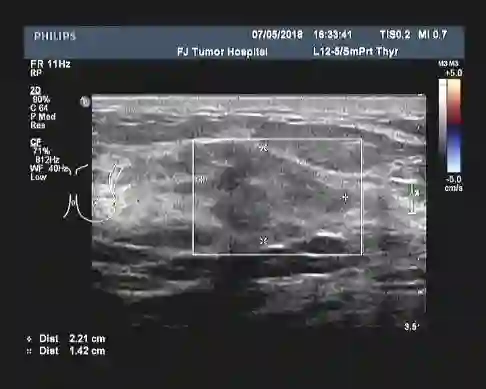

▎疗效评估:B超(2018-05):左乳外上象限探及一低回声区,约5.5cm×5.1cm,形态不规则,边缘不整,可见成角、毛刺,周围可见毛玻璃改变,内部回声不均;左腋中下组探及数个低回声,大者约2.6cm×1.9cm,边界尚清,类圆形,皮髓质分界不清,皮质不规则增厚,淋巴结门消失;右乳及右腋窝未见异常。

2.     该患者使用TH方案2周期时,尽管B超提示左乳肿块大小不变,左腋窝淋巴结稍增大,按照RESIST 1.1的标准,疗效评价为SD。本病例中选择继续给予TH方案2周期, 共使用了TH方案4周期后,疗效评价为PD,提示该患者对TH方案不敏感,根据耐药的界定,倾向于曲妥珠单抗的原发耐药。此时,谨慎地予以更换化疗药物,坚持抗HER2治疗,参照NeoALTTO以及NeoSphere的研究,果断进行双靶治疗;同时密切监控,一旦无效进展,应果断中转手术,避免失去手术机会。